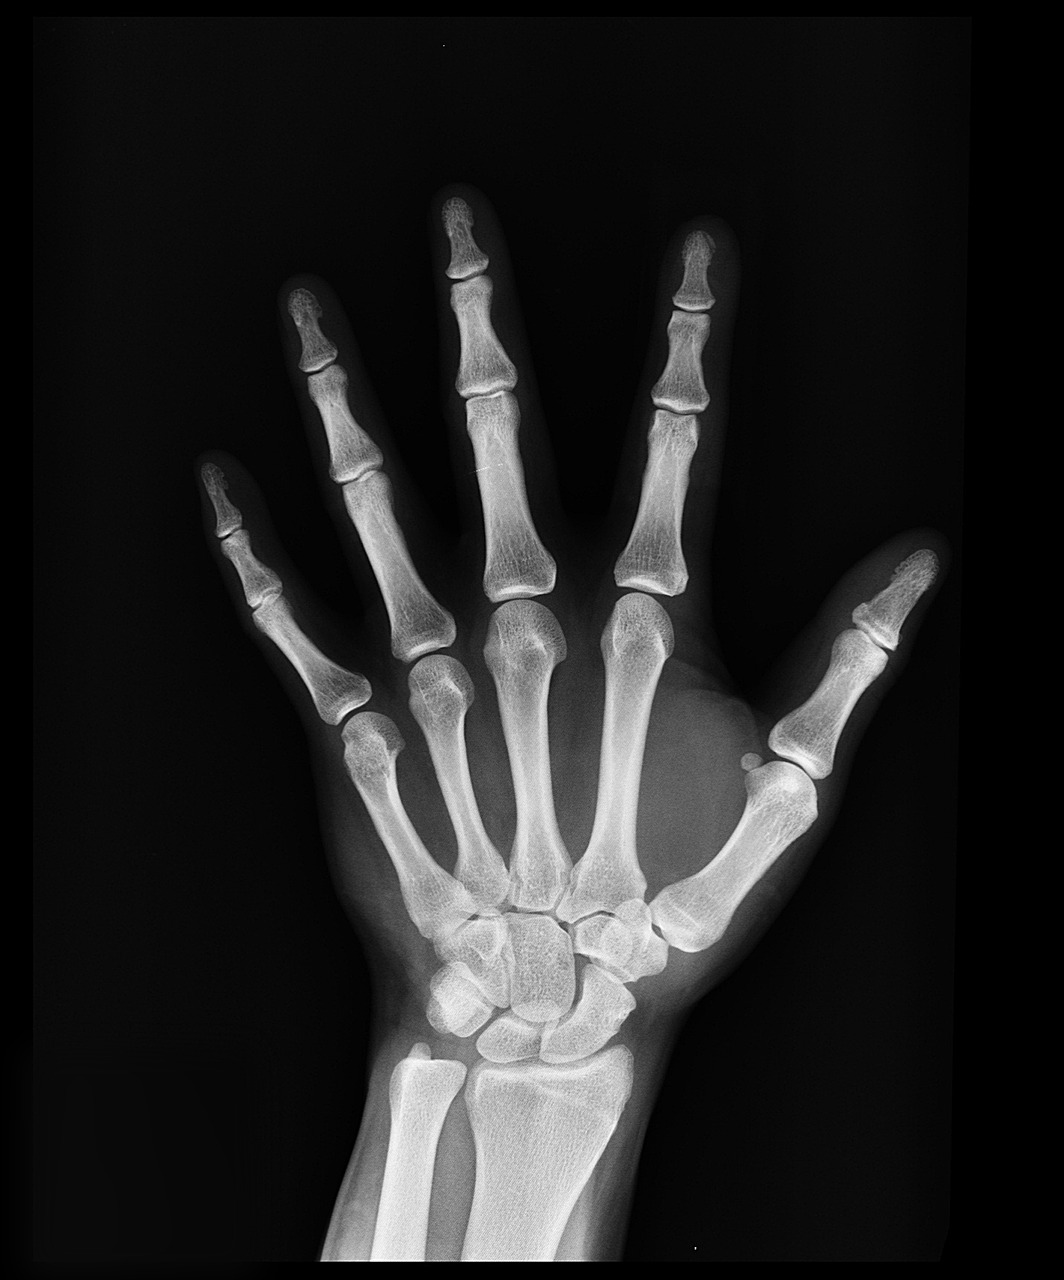

한국 여성의 평균 폐경 시기는 49세로, 이 무렵부터 골밀도 감소가 본격화됩니다. 여성호르몬인 에스트로겐이 줄어들면서 뼈 생성보다 흡수 속도가 빨라지기 때문입니다. 국민건강보험공단 자료에 따르면, 2023년 기준 50대 이상 여성의 3명 중 1명이 골다공증 진단을 받았으며, 특히 65세 이상 여성의 골다공증 유병률은 67%에 달합니다. 폐경 전후 5년 동안 골밀도는 연간 2~5%씩 감소하며, 이 시기를 방치하면 척추 압박골절, 고관절 골절 등의 심각한 합병증으로 이어질 수 있습니다. 특히 폐경 초기에 골다공증이 급격히 진행되는 만큼 조기 검진과 예방이 중요합니다. 질병관리청은 폐경기 여성에게 정기적인 골밀도 검사(DEXA)를 권장하며, 증상이 없어도 조기 진단이 중요하다고 강조하고 있습니다. 또한 폐경기 여성의 골다공증 위험은 흡연, 음주, 운동 부족, 칼슘 섭취 부족 등 생활습관과 밀접한 관련이 있는 것으로 나타났습니다.

국민건강영양조사(KNHANES)에 따르면, 2023년 기준 50세 이상 한국 여성의 골다공증 유병률은 약 35%에 달하며, 70세 이상은 60%를 초과합니다. 골다공증으로 인한 고관절 골절은 전체 여성 골절 중 약 45%를 차지하며, 이는 입원과 사망률 증가에도 직결됩니다. 골다공증은 연령이 증가할수록 유병률이 급격히 상승하지만, 문제는 초기 증상이 거의 없어 진단이 늦어진다는 점입니다. 대부분은 골절 후 병원을 찾아 진단을 받게 되며, 이때 이미 뼈 손상이 심한 경우가 많습니다. 특히 척추 압박골절은 키가 줄어드는 등의 증상을 통해 뒤늦게 발견되곤 합니다. 질병관리청은 골다공증을 "조용한 질병"이라고 표현하며, 조기진단이 생명을 좌우할 수 있다고 경고합니다. 이를 위해 만 54세 이상 여성은 2년에 한 번 골밀도 검사를 받는 것이 권고됩니다. 하지만 실질적으로 골밀도 검사를 받은 여성은 전체 중 약 40%에 불과해 인식 개선이 시급한 실정입니다. 한국은 현재 골다공증 관련 건강보험 적용 범위를 확대하고 있으며, 비타민 D·칼슘 보충제 지원, 골절 후 재활 프로그램 등 다양한 보건 정책을 시행하고 있습니다. 이와 함께 개인의 건강 습관 관리가 병행되어야 실질적인 예방 효과를 기대할 수 있습니다. 한국 중년 여성의 골다공증은 매우 높은 유병률을 보이며, 폐경기 전후의 관리가 핵심입니다. 인구집단별 차이를 이해하고, 정기 검진과 생활습관 개선으로 뼈 건강을 지켜야 합니다. 골다공증은 조용하지만 치명적인 질환입니다. 지금부터라도 나와 가족의 뼈 건강을 챙기기 위한 실천이 필요합니다.